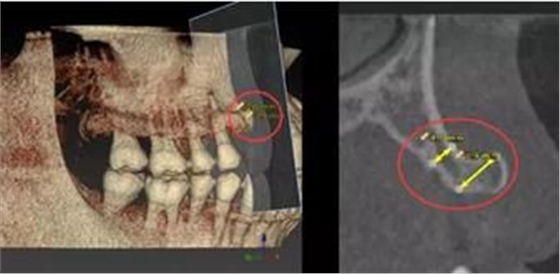

2000年以后,數(shù)字化種植技術(shù)日臻成熟,特別是CBCT(錐形束CT)的普及,使數(shù)字化種植技術(shù)在歐美發(fā)達(dá)國(guó)家得到了日益廣泛的應(yīng)用。數(shù)字化種植技術(shù)是指以患者CT影像信息和相關(guān)修復(fù)信息為基礎(chǔ),借助專(zhuān)業(yè)種植設(shè)計(jì)軟件,進(jìn)行術(shù)前診斷和種植方案規(guī)劃;通過(guò)牙種植手術(shù)導(dǎo)向模板,將術(shù)前制訂的種植方案準(zhǔn)確應(yīng)用于種植手術(shù)和即刻修復(fù)的全過(guò)程,實(shí)現(xiàn)以修復(fù)為驅(qū)動(dòng)的種植手術(shù)。

錐形束CT(CBCT)的普及,精度大大提高;

錐形束CT(CBCT)為重建三圍模型提供精準(zhǔn)數(shù)據(jù)

計(jì)算機(jī)輔助設(shè)計(jì)軟件輔助醫(yī)生定制精準(zhǔn)方案